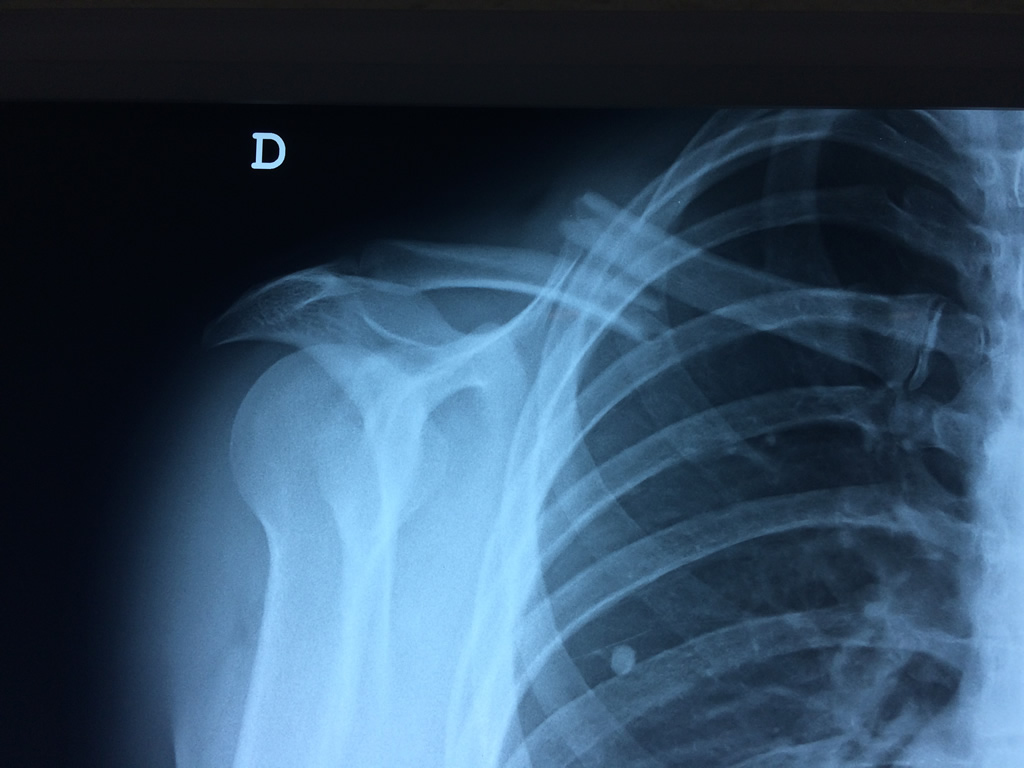

Cirugías de Codos - Clavícula